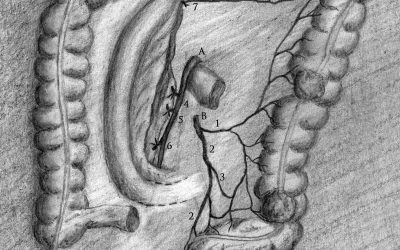

Resezione colica segmentaria sinistra con conservazione dei vasi mesenterici inferiori per adenocarcinoma tra colon discendente e sigma: indicazioni e aspetti tecnici

di Enrico Ganz Scopo di questo scritto è di analizzare le indicazioni e gli aspetti tecnici di una resezione colica segmentaria sinistra con conservazione dei vasi mesenterici inferiori, prendendo spunto da un caso di adenocarcinoma T1 localizzato tra colon...